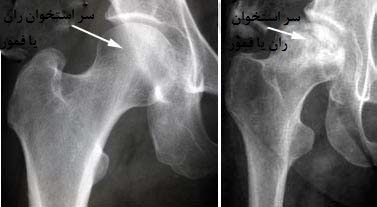

یکی دیگر از عوارض جدی، نکروز آواسکولار سر استخوان ران است. در این عارضه، به‌دلیل کاهش جریان خون به استخوان، سلول‌ های استخوانی از بین می‌ روند و مفصل ران دچار درد شدید و محدودیت حرکتی می‌ شود.